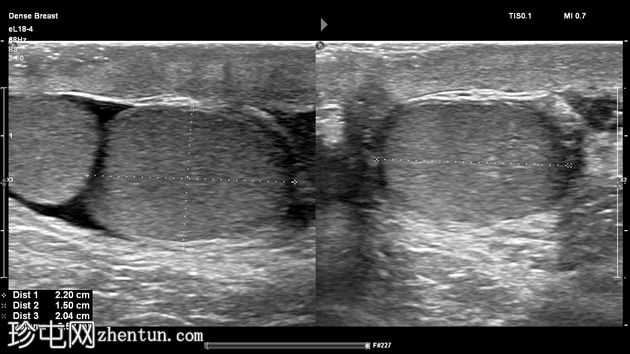

右侧睾丸大小、回声和血流均正常,内部未见病变,体积为4毫升。其附睾正常,未见鞘膜积液。

仰卧位静息状态和站立进行Valsalva动作时,蔓状静脉丛直径均保持在1.9毫米以内,因此排除精索静脉曲张。